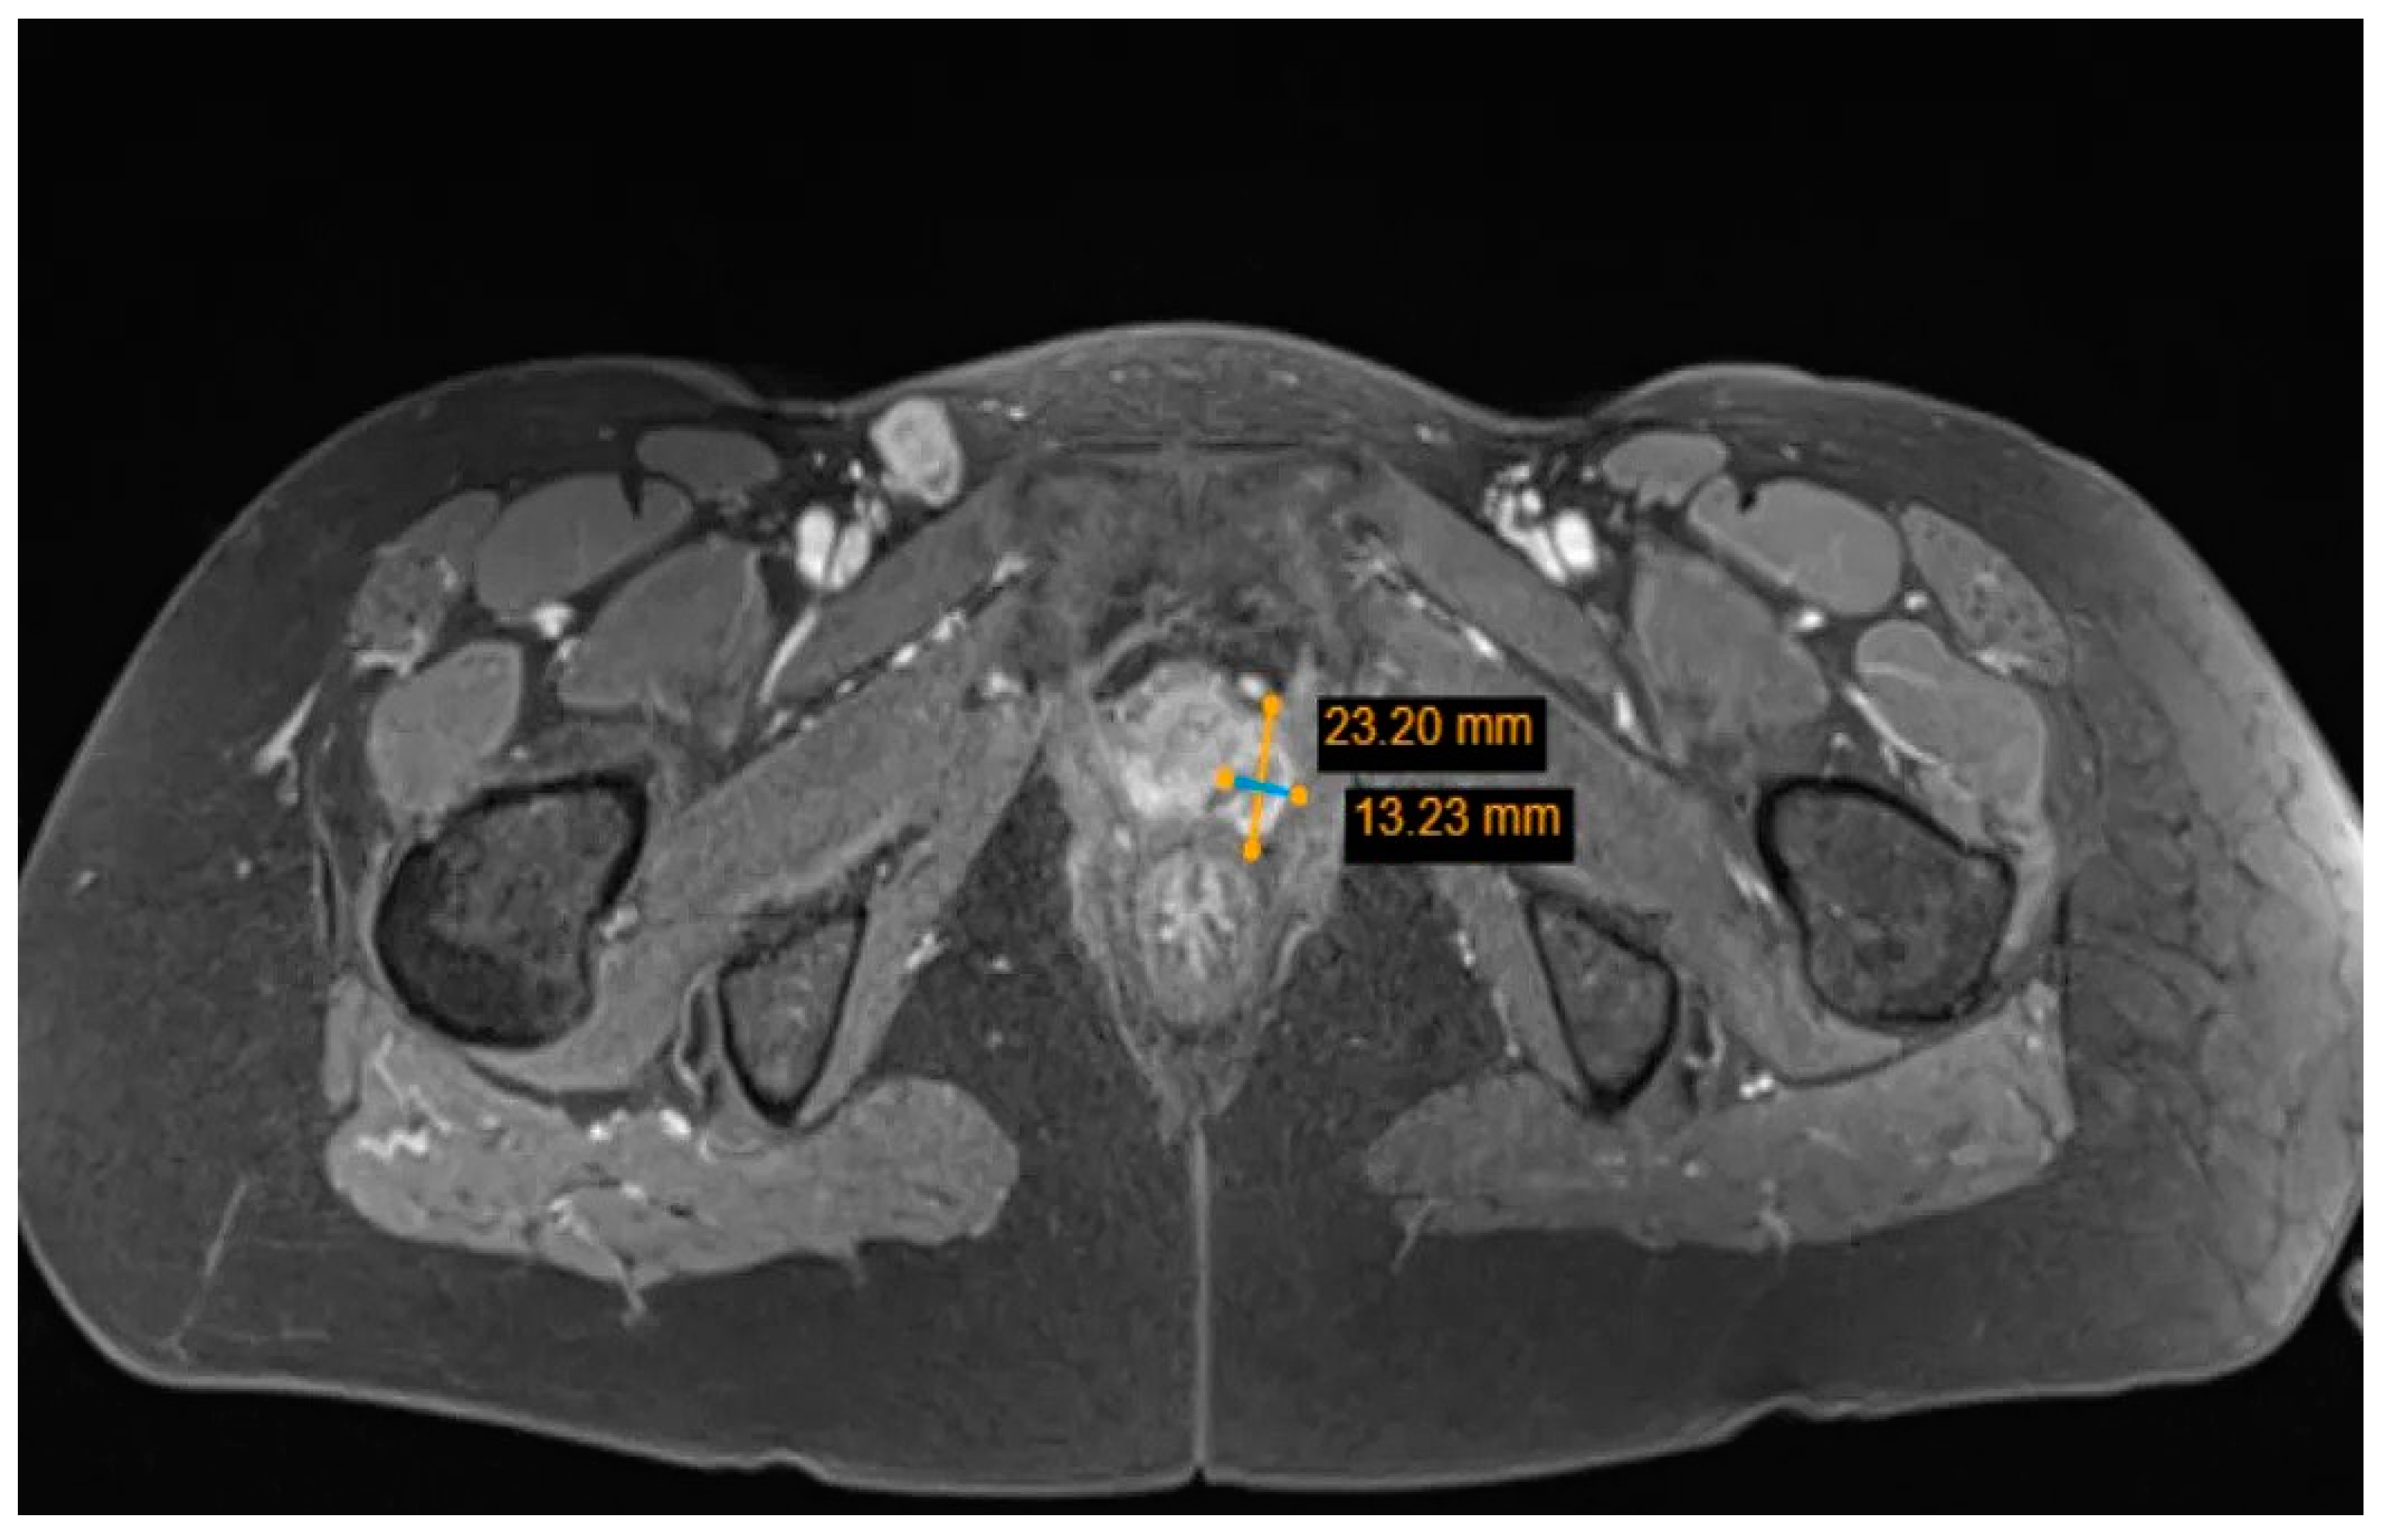

Multiple Rare Primary Malignancies: A Mixed Squamous Neuroendocrine Adenocarcinoma of the Cervix, Metastasized Carcinosarcoma and Extramammary Vulvar Paget’s Disease Case Report

2. Case Report